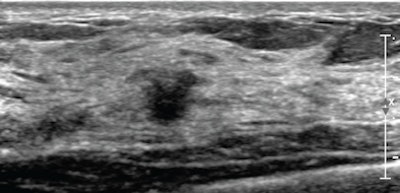

![]() |

| 51-year-old woman: screening whole-breast ultrasound. |